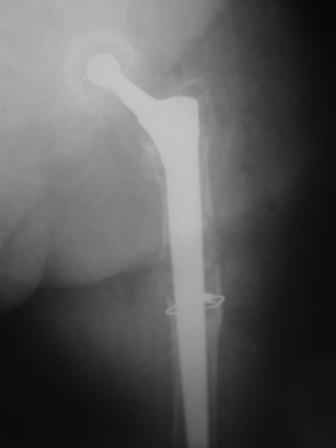

You transformed a cemented hip prosthesis to a cementless revision hip prosthesis with a little approach.

I generally should prefer a long stem revision prosthesis, as that allegated.